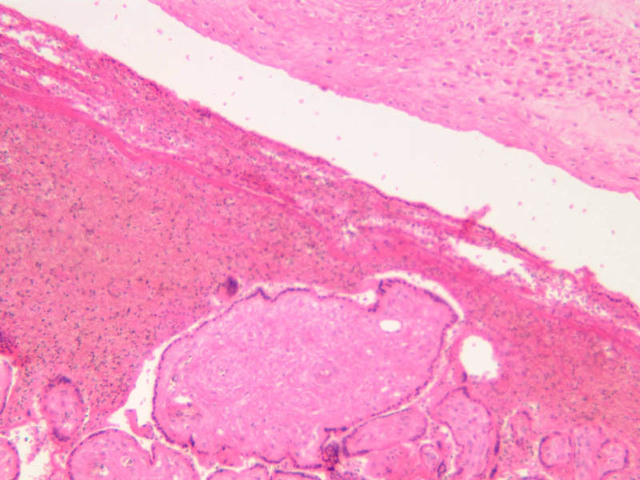

The endometrium of the cervical canal does not slough during the menstrual phase. The glands in this region are relatively large and extensively branched. They are lined by a tall simple columnar epithelium very active in the secretion of mucus. Occasionally these glands become blocked forming Nabothian cysts. The transition of the epithelium of the cervix to that of the vagina is abrupt and is in the region of the external os. At this point, the cervical simple columnar is replaced by the vaginal stratified squamous epithelium (slide B-98 [2.5x-labeled, 10x, 20x, 40x] [2.5x, 10x, 20x, 40x]). This is an area which is commonly inflamed as well as a primary location of cervical cancer.

B98, Uterine Cervix, 2.5x Labeled (H&E) B98, Uterine Cervix, 10x (H&E) B98, Uterine Cervix, 20x (H&E) B98, Uterine Cervix, 40x (H&E) B98, Uterine Cervix, 2.5x (H&E) B98, Uterine Cervix, 10x (H&E) B98, Uterine Cervix, 20x (H&E) B98, Uterine Cervix, 40x (H&E)

Uterine Cervix Table of Identifications

Row Structure Abbreviation Optimal Stain Representative Section Note

1 Cervical Glands (none) H&E b98 cervix vagina junction 2x labeled.jpgB98, Uterine Cervix, 2x

2 Cervix (none) H&E b98 cervix vagina junction 2x labeled.jpgB98, Uterine Cervix, 2x

3 Vagina (none) H&E b98 cervix vagina junction 2x labeled.jpgB98, Uterine Cervix, 2x

4 Stratified Squamous Epithelium (none) H&E b98 cervix vagina junction 2x labeled.jpgB98, Uterine Cervix, 2x